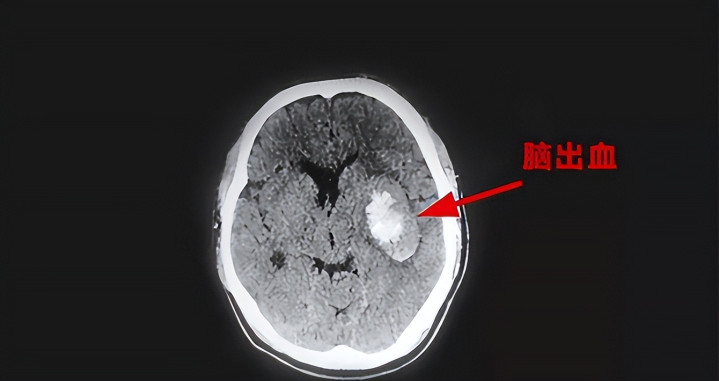

脑部CT是一种高效的影像搜检技能,常用于排查脑出血、脑梗死、颅脑外伤、肿瘤等病变。临床上,医师凭据CT效能制定诊疗决议。但不少患者在搜检达成后,只热心当下的论断,却忽略了搜检自己可能暴涌现的其他伏击健康信号。

无症状腔隙性脑梗塞进击忽视

CT中若请示“腔隙性脑梗”“堕落性脑梗死”,而患者并无彰着症状,是否就不错忽略?谜底是狡赖的。

腔隙性脑梗是脑内轻细动脉紧闭所致的局灶性脑组织缺血坏死,常见于高血压病史较长的中老年东说念主。固然早期可能莫得彰着发达,但永恒累积可导致领略功能着落以致血管性古板。